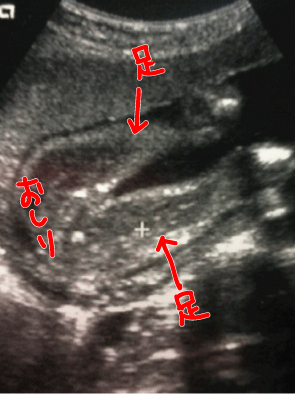

昨日、7月11日(日)は妊婦検診やった。

ずっと気になっていた

3人目の性別。

私 : 先生、性別がわかったら教えてください。

先生 : もちろん、わかったら言うよ。一緒にみよう!

早速検査が始まった。

よーーくよーーくよーーーく!!!!

目を凝らしてお股を確認するけれど

男の子に見えない。

私 : 先生、コレ何にもついてないですか?

先生 : うーーん。多分、これが子宮だと思うんだけど

まだ小さいから何とも言えないなぁ。

私 : えっ。ほんなら女の子の割合の方が高いんですか?

先生 : うーーん。そうだねーー。

・・・・・・・・と、歯切れの良くない感じでした(笑)

次は2週間後です。子宮が見えれば女の子確定かなぁーー。

エコー写真の達人の方がいらしたら、どっちか教えてください(笑)

うちは、2人とも生まれるまで「たぶん女の子だと思います」と言われて、確定はしてもらえませんでした。けえこさんのエコー写真を見る限り、うちの子よりもはっきりとお股が見えているので女の子確率は80%くらいですかね?(笑)